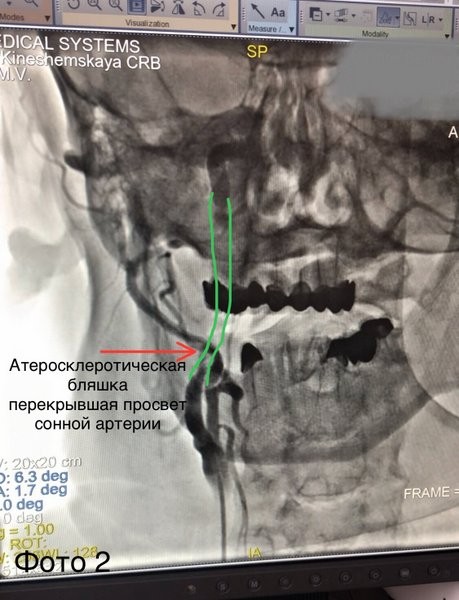

Причиной инсульта послужил «разрыв» атеросклеротической бляшки сонной артерии (фото 2) и, как следствие, тромбоз мозговой артерии (фото 1).

«Пациента взяли в операционную. По данным ангиографии в правой средней мозговой артерии визуализирован тромб (фото 1). Выполнили тромбоаспирацию (удаление тромба) из средней мозговой и стентирование сонной артерии (фото 3) с полным восстановлением кровотока по мозговым артериям (фото 4). Сразу после оперативного вмешательства пациент пришел в сознание. Далее наши специалисты: реаниматологи, неврологи, реабилитологи продолжили бороться за жизнь пациента. 16 дней командной работы позволили спасти его жизнь и восстановить работу мозга», — рассказал Михаил Лапин, заведующий отделением рентгенохирургических методов диагностики и лечения.